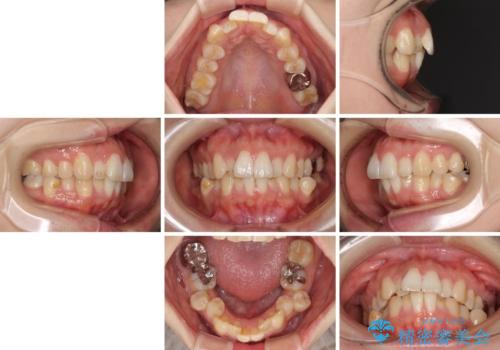

- 前歯のデコボコを気にして来院された患者様です。

非抜歯矯正にて治療を行うと、仕上がりで口元が突出する可能性があったため、小臼歯抜歯での矯正治療を行うこととしました。

上顎は左右の第一小臼歯2本を、下顎は左右の第二小臼歯2本を抜歯して、口元が突出しないようにしながら、奥歯の咬み合わせを改善していく治療計画としました。